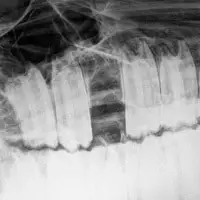

- Digitales Röntgen: Darstellung der Zahnwurzeln, der Kieferknochen und Nasennebenhöhlen